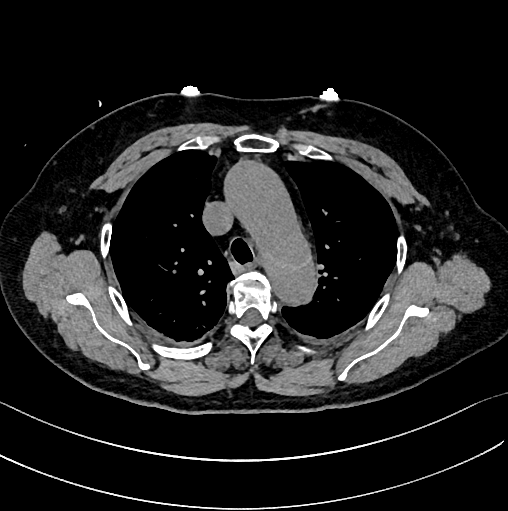

下图的胸部CT平扫,有什么致命的问题?

仔细一看,主动脉里面有线样阴影!并且,线样阴影两边的密度一高一低!